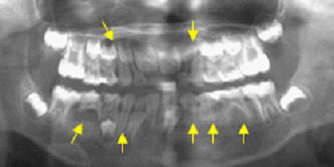

最後比較麻煩的是多數恆牙胚先天性的缺牙,原因不是很清楚,大部分和遺傳有關,小朋友如果有這種情形時,家長也常有相同的缺牙狀況(如圖七),缺牙數目少則三、四顆,多則十幾顆,治療上也相對困難。小朋友的治療大部分以保留乳牙為最主原則,能使用多久就用多久,之前也提過成人仍保有乳牙的情形也是常見的。如果不幸脫落後也不用太擔心,現在植牙技術很發達,大部分都可以解決的。只是小朋友因為還再生長的關係,必須等到齒槽骨生長結束,才能進行植牙。

先天缺恆牙胚(圖七)